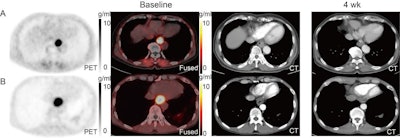

In a small clinical trial, Chinese researchers at the Shandong Cancer Hospital and Institute in Jinan, Shandong, investigated whether F-18 FAPI-04 PET/CT scans can predict outcomes in patients with locally advanced esophageal squamous cell carcinoma (LA-ESCC). The scans revealed which patients responded poorly to chemoradiotherapy and suggests the approach may be useful for screening patients before treatment.

This trial was conducted between June 2021 to March 2022 and included 18 patients with LA-ESCC who underwent F-18 FAPI-04 PET/CT imaging before chemoradiotherapy. Four weeks after treatment, patients were split into groups to determine who showed a complete response, partial response, stable disease, or no response.

The researchers evaluated standard uptake (SUV) values based on tumor uptake of the F-18 FAPI-04 radiotracer, as well as target-to-background ratios (TBR) between the groups. At baseline, quantitative measures of patient response were significantly higher in those patients who did not respond to treatment compared to those who did -- specifically TBRblood (12.53 vs. 10.29), TBRmuscle (12.24 vs. 9.81), and SUVmean (14.30 vs. 4.25), Yuan's group reported.